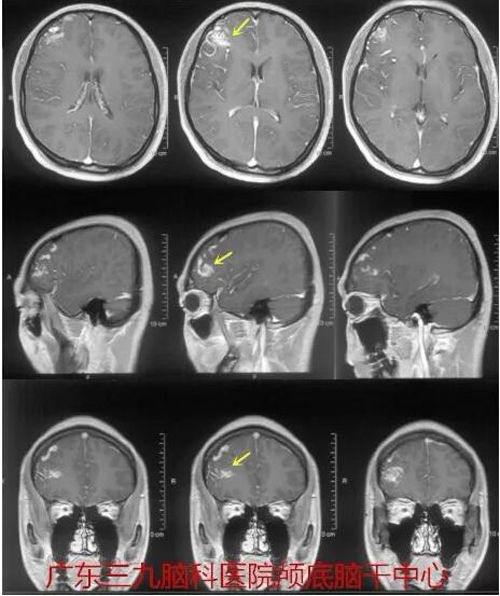

图1:外院术前磁共振示右侧额叶一迂曲血管团。